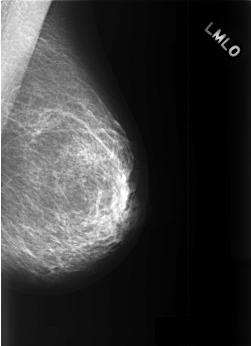

C_0377_1.LEFT_MLO

LEFT_MLO LINES 5528 PIXELS_PER_LINE 4008 BITS_PER_PIXEL 12 RESOLUTION 50 NON_OVERLAY